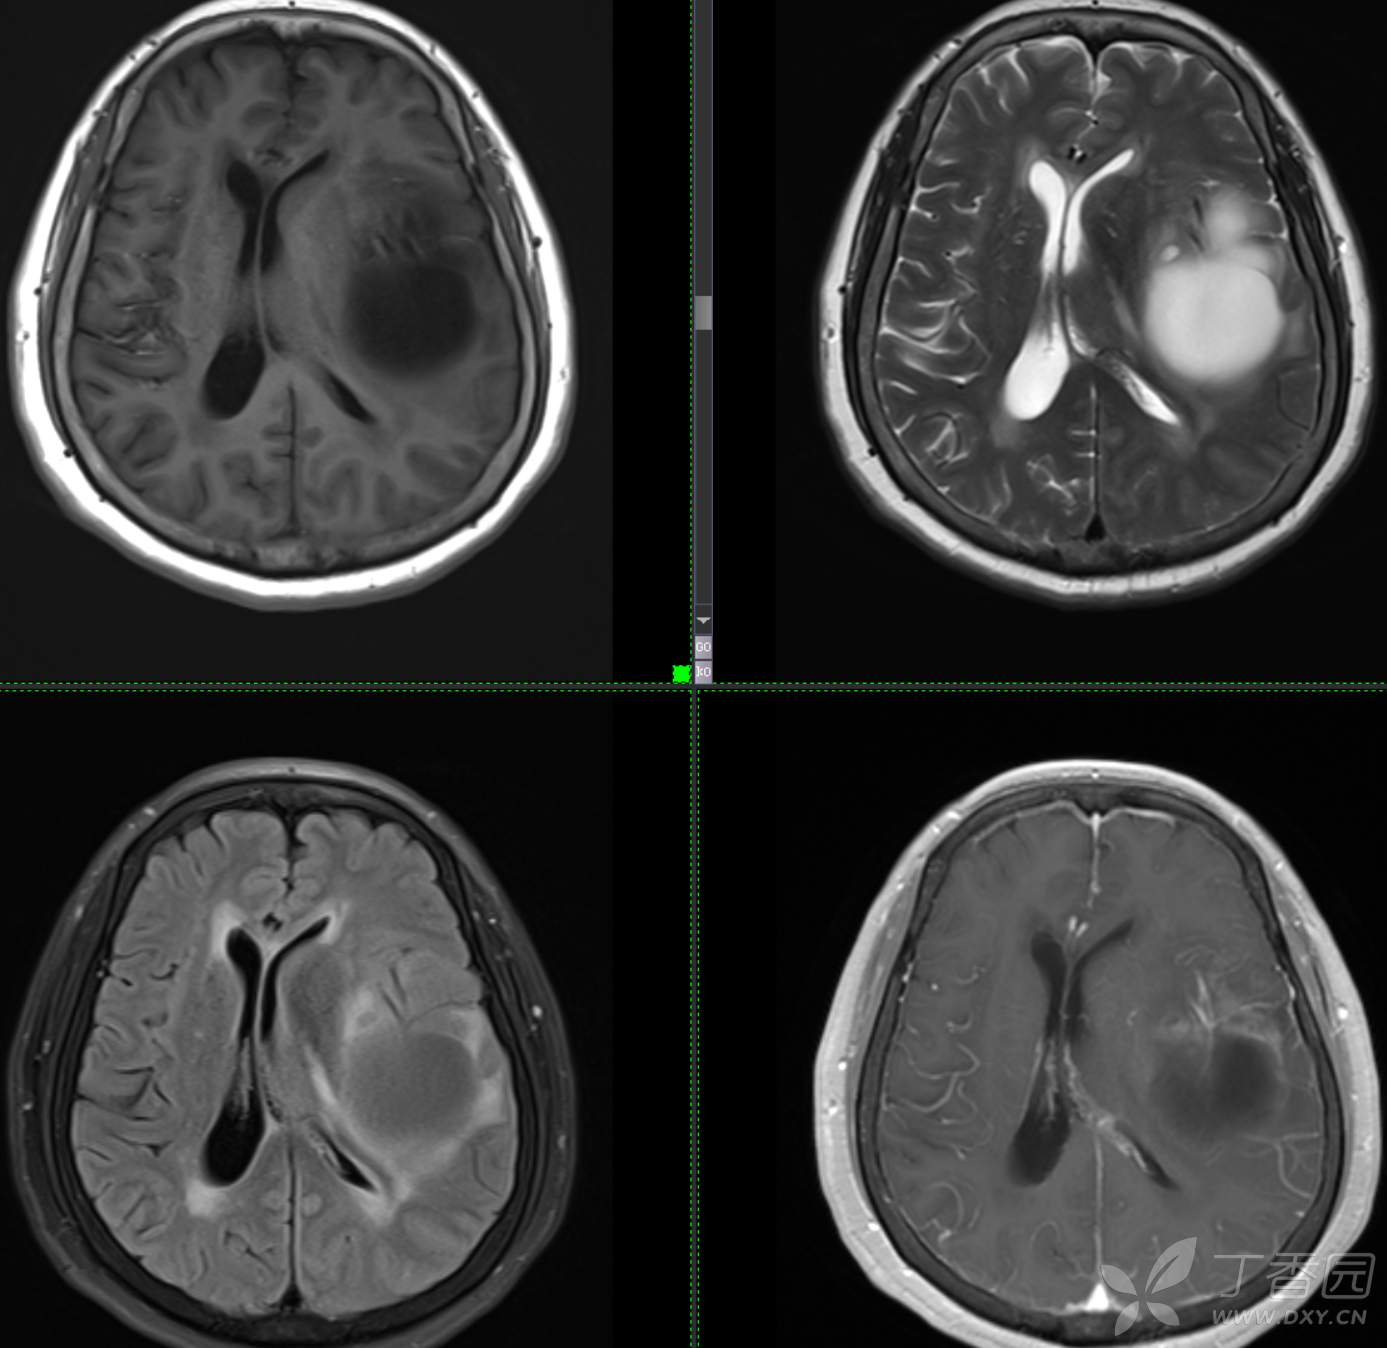

现病史: 【患者1月余前无明显诱因出现记忆力减退,易忘记事情,表现为忘记说过的话、易忘 事、理解力及计算力均尚可、阅读无受限、无性格脾气改变,无头痛头晕、无恶心呕吐、无视物模糊,无言语不利,无幻觉妄想,当时未重视未就诊。1月内记忆力减退进行性加重,对刚做过的事情即遗忘,计算力下降,日常生活尚能自理。遂至我院门诊就诊,查“颅脑CT平扫:左侧基底节-颞叶区低密度占位,建议进一步增强 MRI检查。

患者既往子宫内膜癌手术史;高血压病史3年